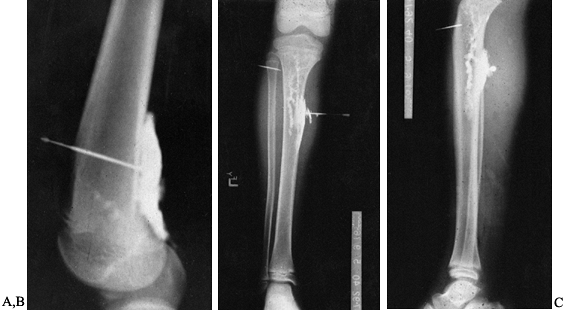

bone grafting six or more weeks later. The muscle flap can be elevated

and cancellous bone grafting performed underneath, provided there are

no signs of infection (Fig. 133.12).

Figure 133.12. Anteroposterior (A) and lateral (B)

radiographs of the tibia and fibula in a 21-year-old man who had a previous posterior bone graft and now shows the presence of a large sequestrum. Lateral film (C) shows debridement of the infection and sequestra. Lateral film (D) taken 10 months after a local flap was performed and an autogenous cancellous bone graft was performed. |

more likely to be successful. For defects up to 6 cm, autogenous

cancellous bone grafting can be done (Fig. 133.13).

Figure 133.13. A: Anteroposterior radiograph of a 34-year-old woman with approximately a 6 cm defect. B:

Anteroposterior and lateral films taken 1 year following performance of an autogenous cancellous bone graft to fill dead space caused by bony defects. |